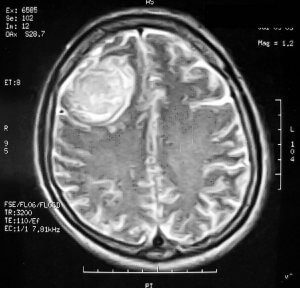

- Компьютерная томография, магнитно-резонансная томография – исследования позволяют узнать о точном расположении менингиомы.

- Магнитно-Резонансная Томография (МРТ)